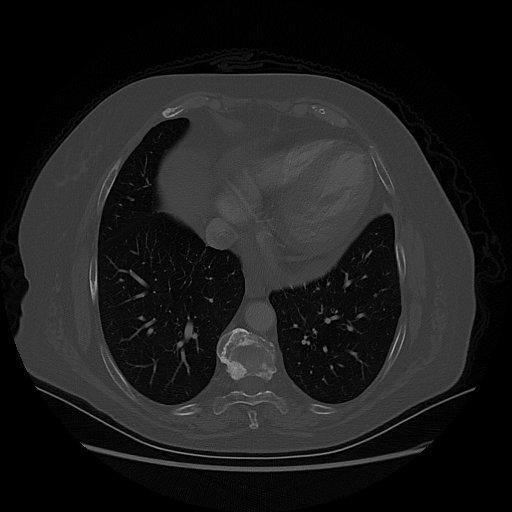

Original NATIVE CT scan (input)

Mediastinum window (WL 40, WW 400 β†’ Low βˆ’160, High +240)

Reconstructed NATIVE CT scan (cycle consistency)

Original VENOUS CT scan

Generated VENOUS CT scan (A→B translation)